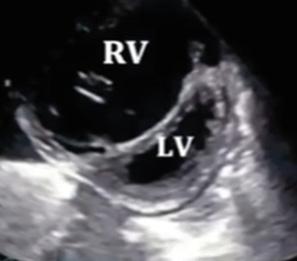

Ecocardiograma:

Aumento inexplicable de un espesor de la pared del ventrículo izquierdo ≥ 15 mm.

En las formas obstructivas, se observa el movimiento anterior sistólico (SAM) de la válvula mitral.